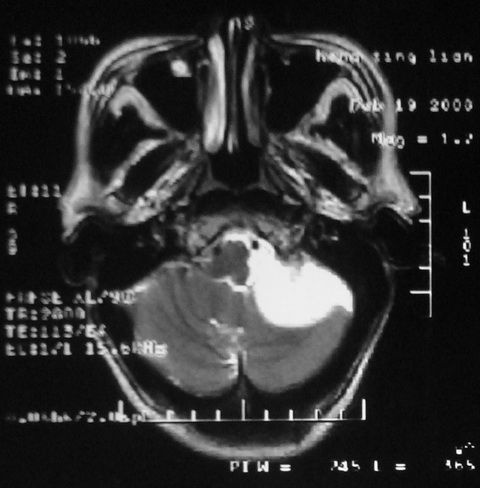

m,72,头疼,头晕两年,伴视力模糊三月,饮食呛咳两天。pe:颈部抵抗,左眼突出,左眼瞳孔约3mm,对光反射消失,双眼失明,伸舌困难,双肺呼吸音粗,心率110次/分,左上肢肌力i级,左下肢屈曲,肌张力高。现有08年2月19mri平扫及10年2月8日mri增强请会诊。ct病灶呈低密度伴散在点、片状等密度区,无明确钙化(无ct片资料可供上传)。[

脑外肿瘤,表皮样囊肿可能性大。

脑外肿瘤,囊实性,环状不规则强化,内听道扩大,考虑神经源性肿瘤

考虑表皮样囊肿。

左侧桥小脑区占位伴梗阻性脑积水----考虑 1神经鞘瘤 2室管膜瘤。

左侧桥小脑区神经鞘瘤伴梗阻性脑积水。

听神经瘤

脑外肿瘤,病灶呈匍匐蔓延,表皮样囊肿可能性大。

脑外肿瘤,病灶呈匍匐蔓延,表皮样囊肿可能性大。支持!

左侧桥脑小脑角区肿瘤并脑积水,考虑听神经瘤,脑膜瘤?

考虑听神经瘤

左侧桥脑小脑角区肿瘤并脑积水,考虑听神经瘤,